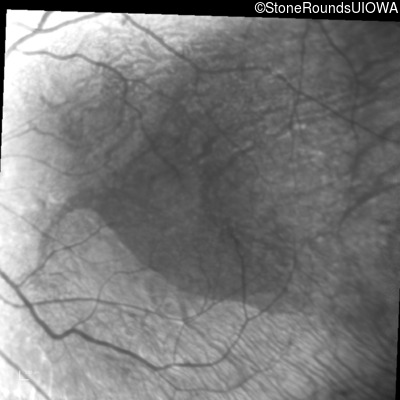

Infrared Fundus Photograph - Right - Light Perception

Exemplar